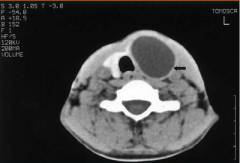

- Фолликулярная аденома. Представляет собой узел округлой формы, покрытый капсулой.

Отличить один вид аденомы от другого можно только при исследовании фрагмента новообразования под микроскопом. Выделяется среди прочих разновидностей своими симптомами только токсическая аденома щитовидной железы.

Чаще при аденоме в толще железы обнаруживается один узел. Реже встречаются множественные узлы.